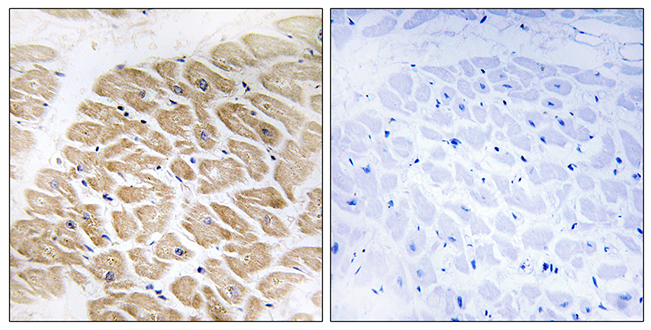

Anti-MOK AntibodyA98312

ApplicationsELISA, ImmunoHistoChemistry

ReactivityHuman, Mouse, Rat

- SizePrice